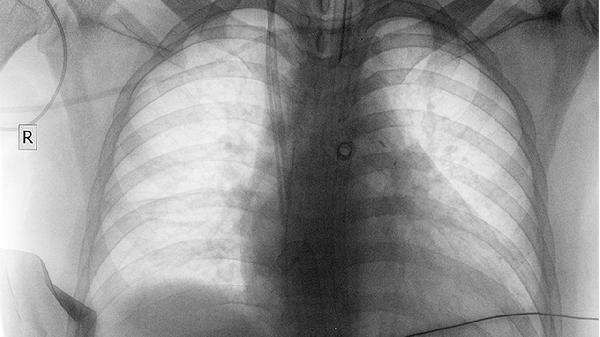

肺部腫瘤SUVMAX4.3通常提示PET-CT檢查中代謝活性較低,多數(shù)情況下可能與良性病變或低度惡性潛能腫瘤有關,少數(shù)情況下需結合病理檢查進一步明確。SUVMAX是標準化攝取值,反映病灶對放射性示蹤劑的攝取程度。

SUVMAX4.3屬于輕度代謝增高,常見于炎性肉芽腫、結核或部分早期肺癌等。炎性病變因局部免疫細胞聚集可能出現(xiàn)假陽性,需結合臨床病史和影像特征綜合判斷。低度惡性腫瘤如類癌或某些腺癌也可能表現(xiàn)為輕中度代謝增高,但通常伴隨邊界清晰、生長緩慢等特點。

極少數(shù)情況下,高分化惡性腫瘤或某些特殊病理類型可能因代謝活性低而呈現(xiàn)類似數(shù)值,需通過穿刺活檢或手術切除明確性質。若患者存在長期吸煙史、家族腫瘤史等高危因素,即使SUVMAX較低仍建議積極隨訪。

建議患者攜帶完整影像資料及病史至腫瘤科或胸外科就診,必要時完善病理檢查。日常需避免吸煙及接觸污染環(huán)境,定期復查胸部CT監(jiān)測病灶變化。